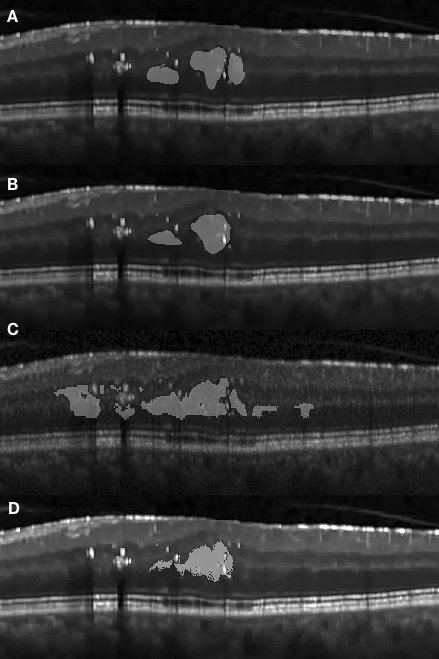

Figure 4.2 (A) shows a concrete edema embedded within retinal layers on the right-hand side of the fovea region. The distinctive features of this edema are not visually recognizable in this OCT image due to low contrast within the retinal layers. However the presence of the edema causes a deformation of the retinal layers on the right-hand side, with a corresponding change of the layer interval, making them noticeably thicker than those on left-hand side. It is observed in Fig. 4.2 (D) that the segmented results obtained with our approach presents a high correspondence to the manually segmented results. However, it is worth noting that our approach has segmented several regions which had been represented separately under manual annotation as a single large one.